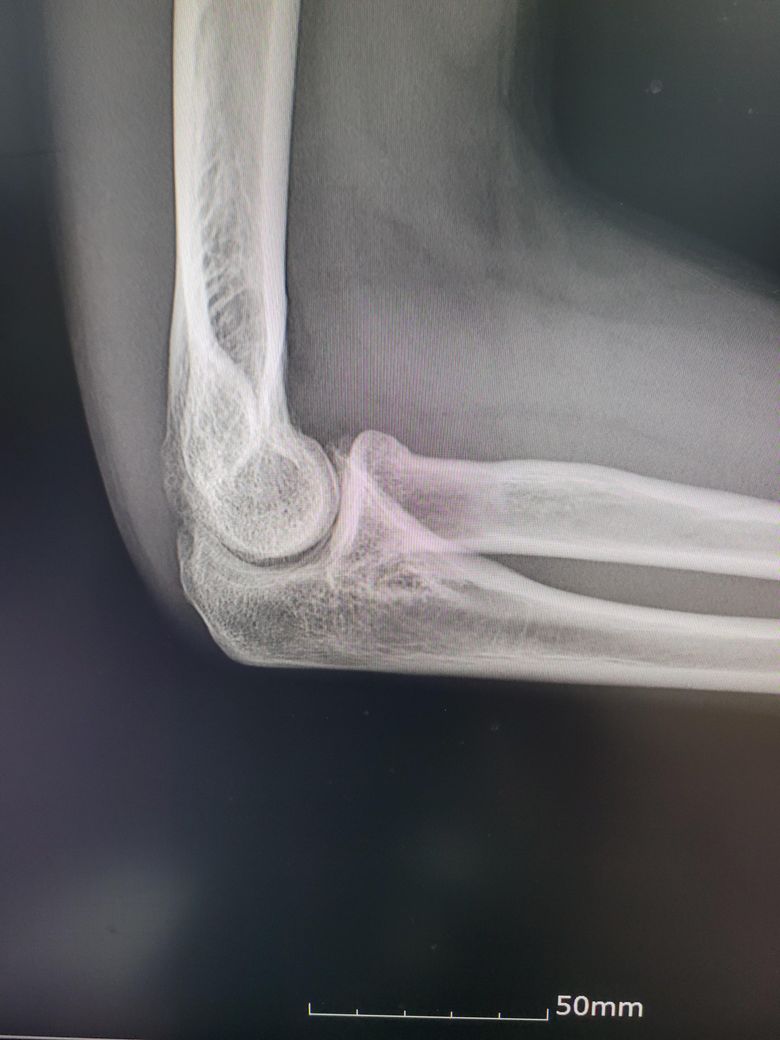

팔이 아파서 여러병원 찾아다니느라 엑스레이 사진도 복사해왔는데 1,2년 전에 비해서 팔꿈치에 동그란 게 생겼더라구여 이게 뭔지 모르겠습니다

과거에 활액막연골종으로 같은 부위를 수술받은 적이 있습니다

첫 번째 두 번째 사진이 가장 최근입니다

• 2번 째 사진